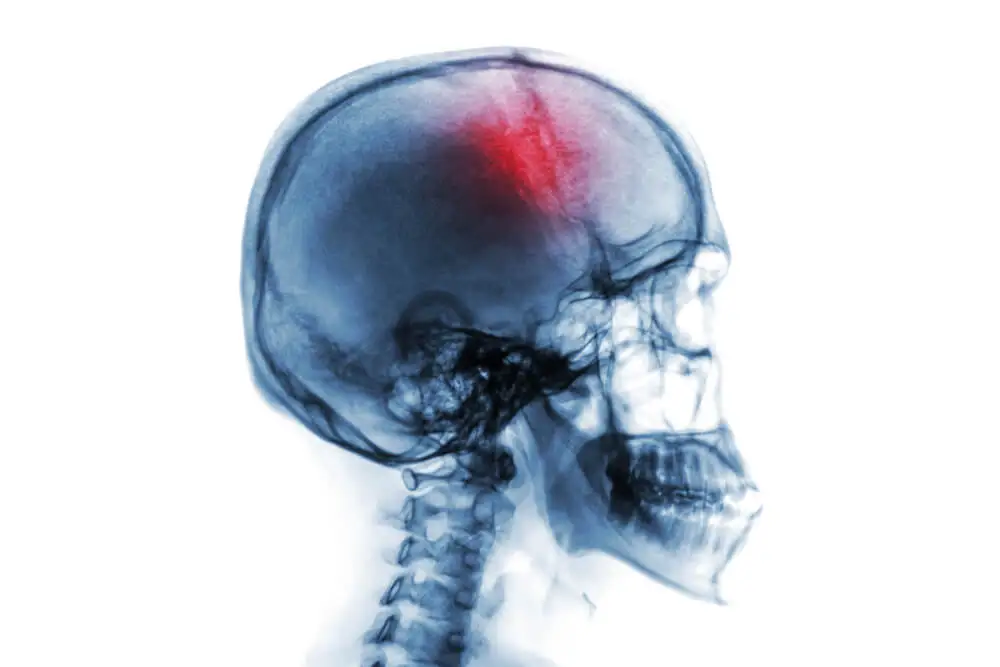

Hemorragia subdural o subaracnoidea

La duramadre y la aracnoides son dos de las tres meninges con que cuenta el ser humano. Las meninges son las estructuras que recubren el sistema nervioso central. Una hemorragia subdural o subaracnoidea se refiere a una hemorragia que ocurre por debajo de cada una de estas dos meninges.

En una hemorragia subdural o subaracnoidea, la circunstancia primera es la salida de sangre de los vasos sanguíneos, que queda almacenada en los espacios entre las meninges. Esto causa daños en el tejido encefálico, generando así diversos cuadros clínicos.

Sin embargo, en función de si la hemorragia es subdural o subaracnoidea, los desencadenantes, el curso de la patología y su clínica serán distintas.